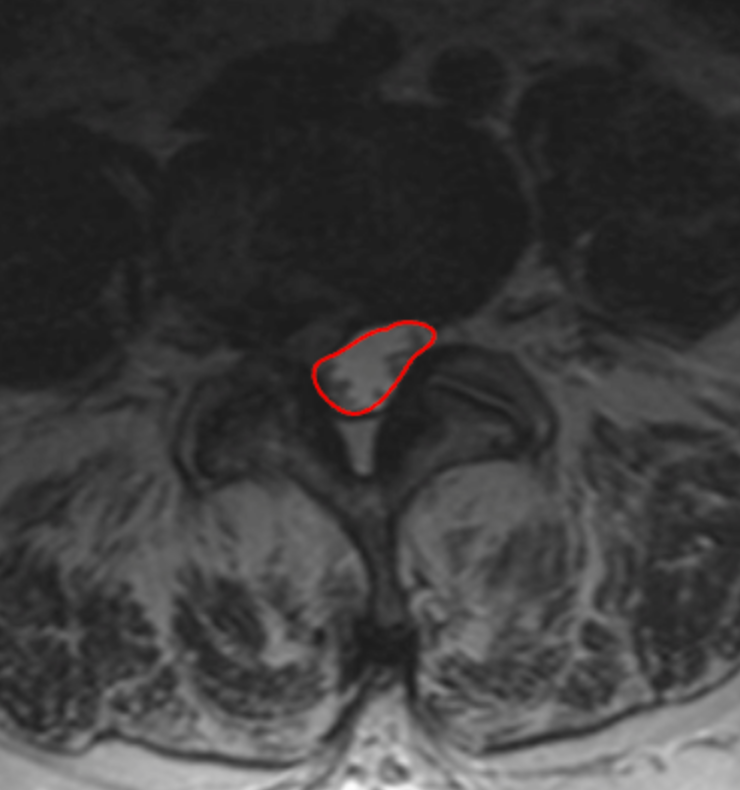

Dural sac CSA quantifies the cross-sectional area of the thecal sac within the lumbar spinal canal and directly reflects neural element compression from disc bulge, ligamentum flavum hypertrophy, facet overgrowth, or spondylolisthesis.

This metric isolates the functional neural space, making it more clinically relevant than osseous canal area when evaluating lumbar spinal stenosis and neurogenic claudication.

• With a freehand ROI tool, trace the outer margin of the dural sac (CSF boundary), excluding epidural fat and ligamentum flavum.

• Close the ROI to calculate the dural sac area in mm².

• Record the smallest CSA across all lumbar levels.

3) Normal vs. Pathologic Ranges

• Normal: > 100 mm2

• Relative stenosis: 75 - 100 mm2

• Severe stenosis: 50 - 75 mm2

• Critical stenosis: < 50 mm2

• CSA < 75 mm² is strongly associated with symptomatic neurogenic claudication.

• CSA < 50 mm² correlates with severe functional limitation.

Dural sac CSA is preferred over bony canal CSA because it reflects true neural compression.